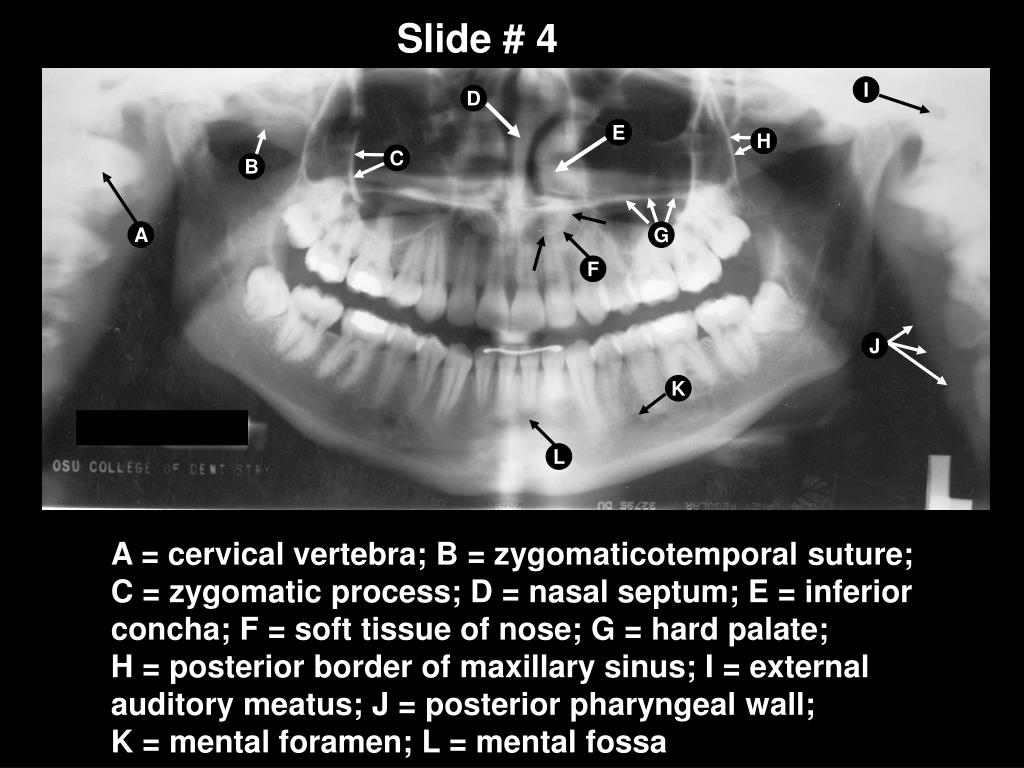

Anatomical Landmarks Of Panoramic Radiographs . Successful interpretation of panoramic radiographs begins with an understanding of the normal anatomy of the head and neck and how it is depicted in this. • determine the cause and appearance of various technique errors. Download scientific diagram | identification of anatomical landmarks on a panoramic radiograph: (1) pterygomaxillary fissure, (2) inferior border of orbit, (3) nasal septum, (4) zygomatic. In this chapter radiological anatomy of intraoral and extraoral radiographs will. • review normal anatomy observed in panoramic images. Learn how to take diagnostic panoramic images and identify normal and abnormal anatomical landmarks. The course covers equipment, patient preparation,. Figure 2 below, includes many of the normal anatomical landmarks that will be visible on a diagnostic panoramic image. Successful interpretation of panoramic radiographs begins with an understanding of the normal anatomy of the head and neck and.